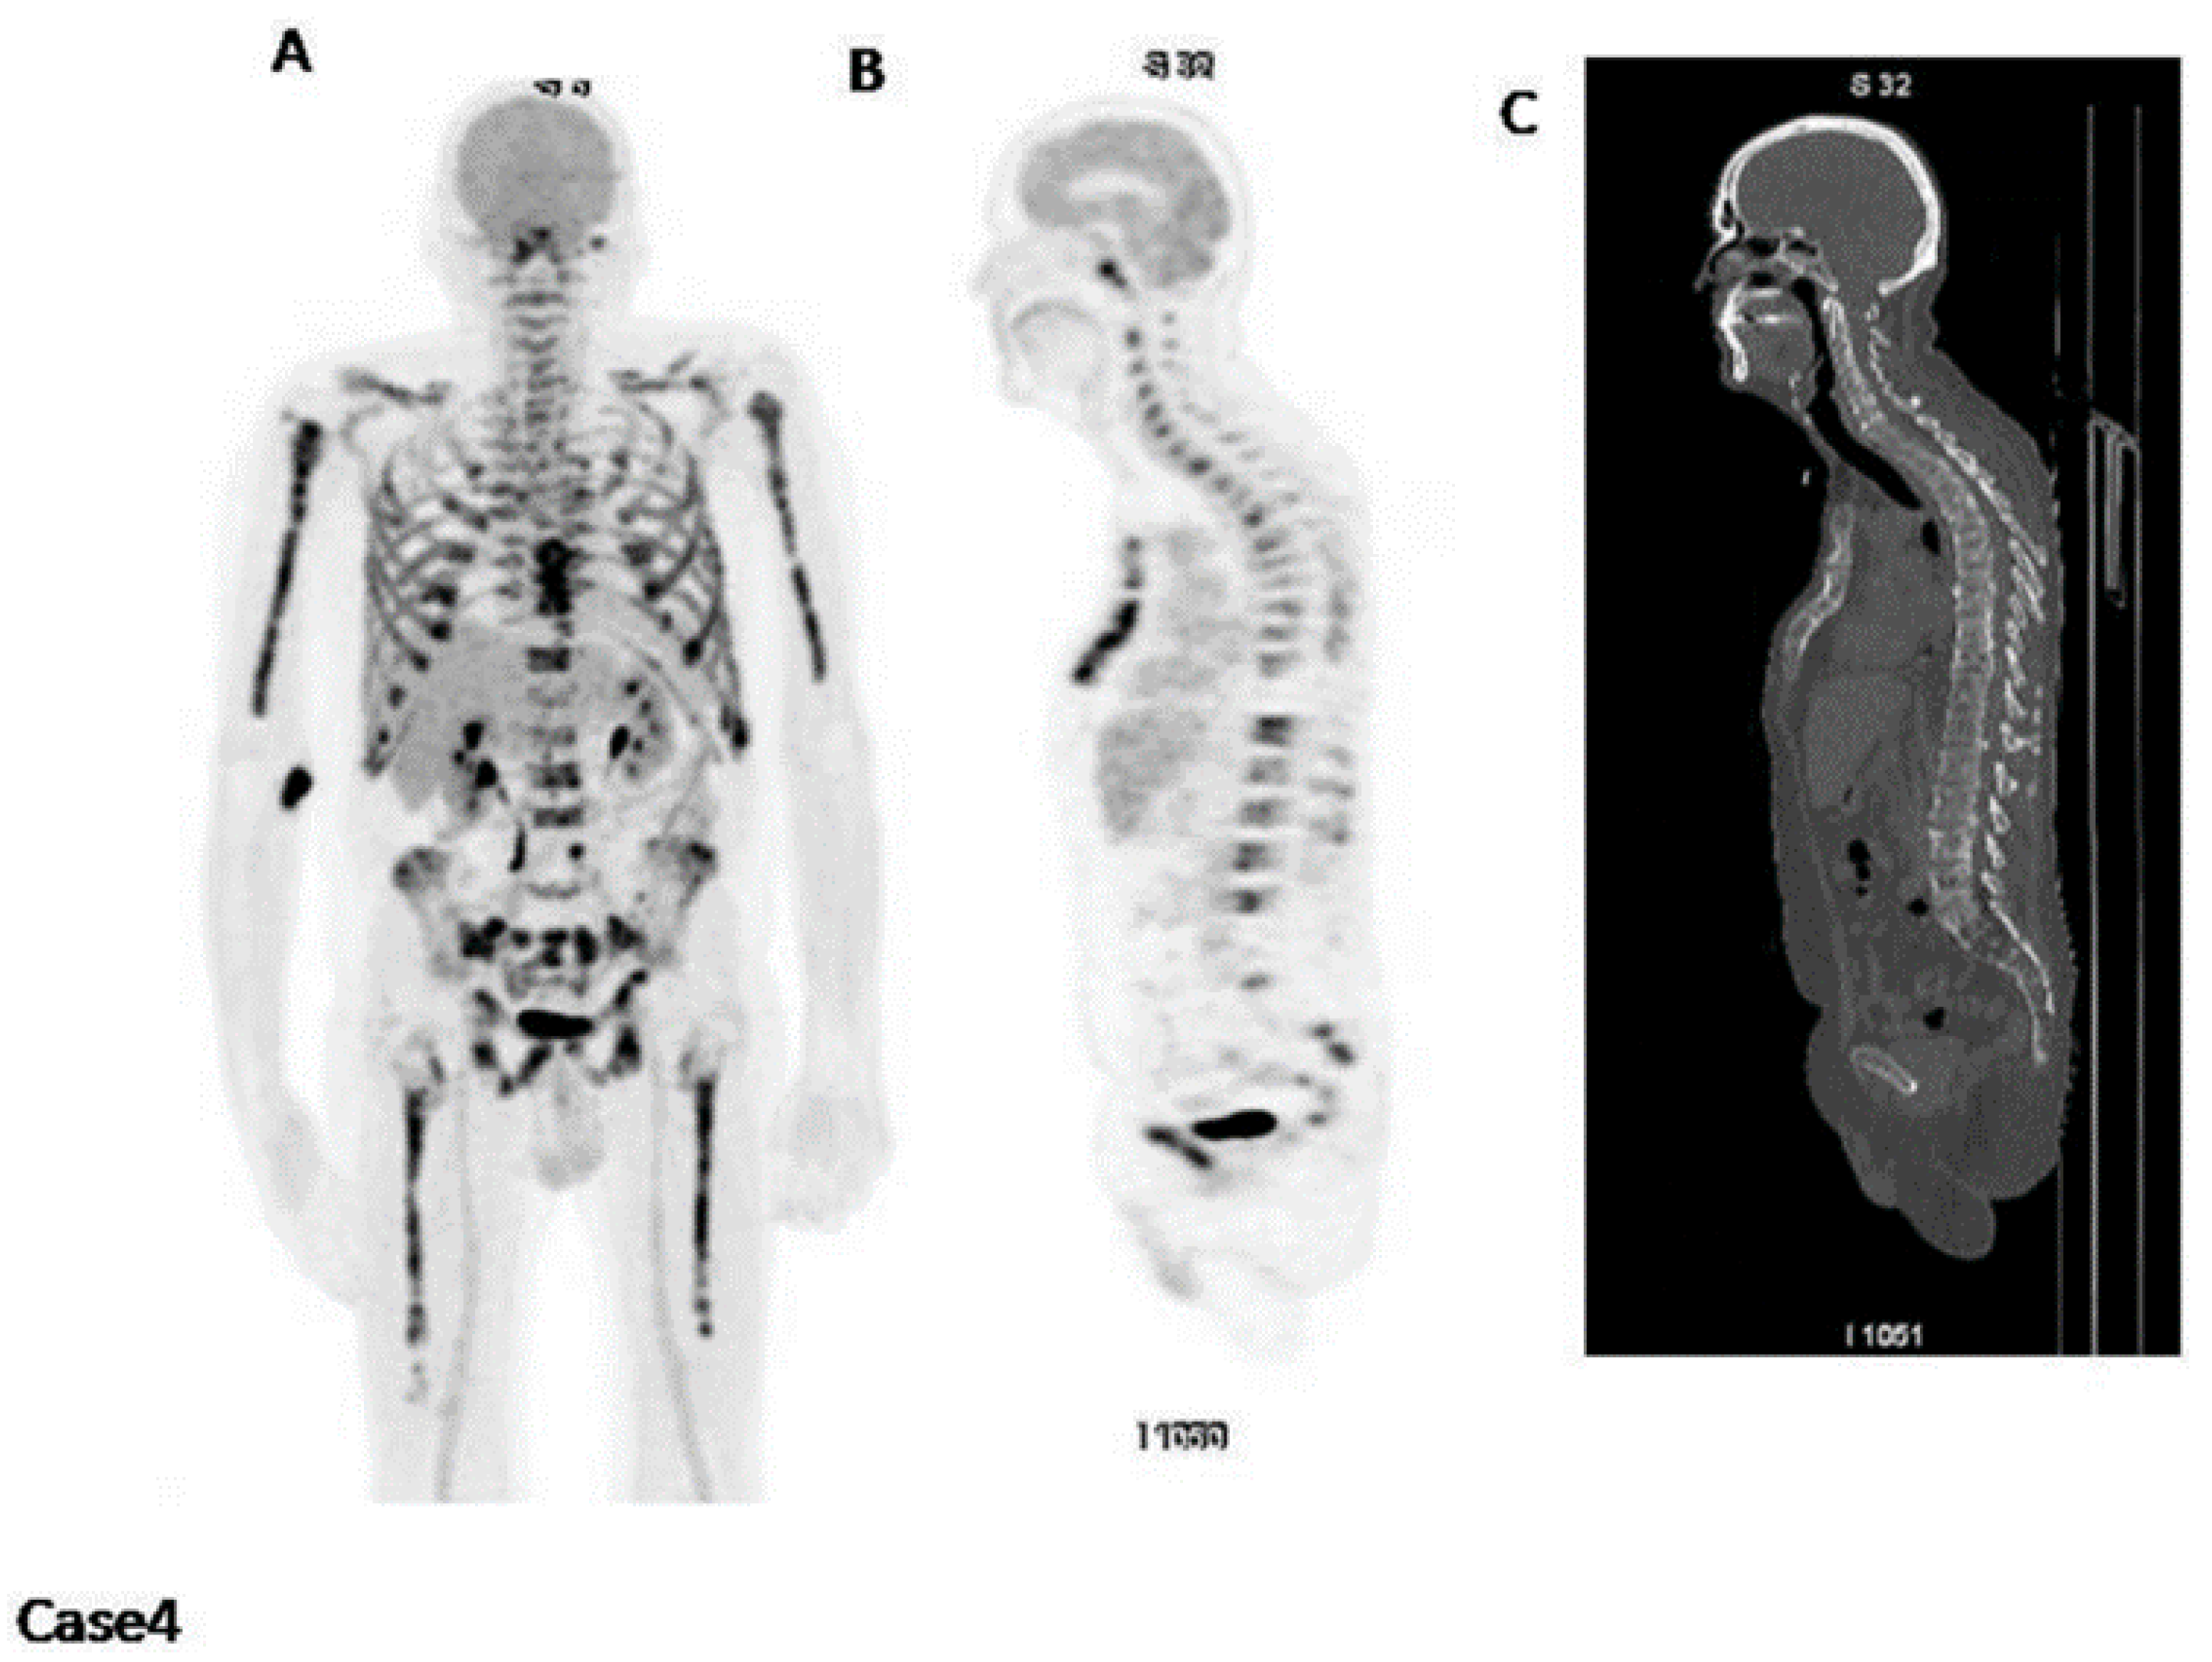

The presence of fluoride in Na[18F]F serves as a direct marker of osteoblastic activity, as it is specifically incorporated into newly formed bone mineral sites that are exposed [41]. Consequently, Na[18F]F PET can be utilized to evaluate bone turnover in different medical conditions. Zirakchian Zadeh et al. investigated the effects of high-dose therapy (HDT) and conventional-dose chemotherapy on the uptake of Na[18F]F in myeloma patients [42]. In total, 19 patients with MM who received HDT and an additional 11 MM patients who received chemotherapy at standard doses were included in the study (Figure 8) [42]. Following HDT, myeloma patients exhibited a noticeable decrease in Na[18F]F uptake in various areas, including the overall skeleton, pelvis, entire femoral neck, and lateral femoral neck. Conversely, in the non-HDT group, no significant alterations were observed (Figure 8) [42]. As a result, the authors inferred that Na[18F]F holds potential for evaluating bone loss in myeloma patients after HDT [42].

Figure 8.

The images on the left depict a semi-automated CT-based segmentation used to assess bone turnover in the entire bone and pelvis of multiple myeloma patients before and after treatment (a,b). Regions of interest were also delineated to evaluate changes in Na[18F]F uptake in the femoral neck of these patients (c). Images obtained from comparison of Na[18F]F uptake in the whole bone, pelvis, and femoral neck of multiple myeloma patients before and after high-dose therapy and conventional-dose chemotherapy, Zirakchian Zadeh et al., EJNMMI, Figures 2 and 5, obtained with permission; reference [42] in this review article.